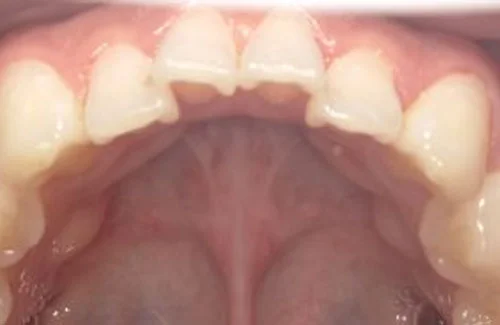

<症例7>歯がガタガタで噛み合わせが悪くお悩み

抜歯無し・マウスピースのみで矯正した症例です。

もともと歯列弓が非常に狭く、V字に近い形をしていたので噛み合わせも非常に不安定でした。

また、下顎前歯部がかなり上の方に生えていたため、下の前歯が上の前歯を突き上げてしまい出っ歯の状態になっていました。

現在では見た目はもちろん、臼歯の噛み合わせも改善しております。

奥歯の患者様も大喜びでした。

患者様と症状

主訴:歯のガタガタ、噛み合わせが悪い

性別・年齢:20代女性

問題点:叢生(重度)、V字歯列弓、ディープバイト

診断:前歯部の叢生を伴うアングルⅠ級、骨格性Ⅰ級の不正咬合

主なリスク:臼歯の移動に伴い一時的に咬合しにくくなる、歯肉退縮

症状:叢生(そうせい) 過蓋咬合(かがいこうごう)

治療内容

治療期間:1年10ヶ月

治療費用:990,000円(税込)

プラン:Full2プラン

抜歯:無し

再診治療費:無し

追加治療費:無し

保定装置費:無し

治療前後の写真